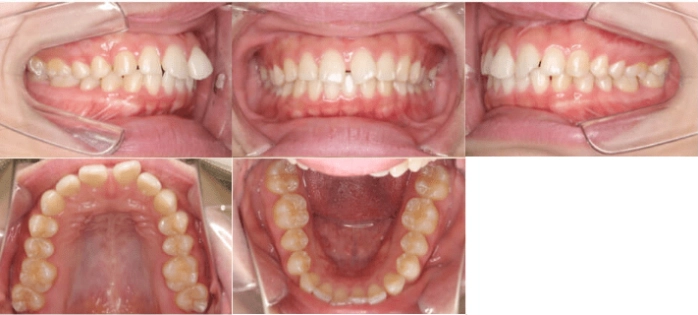

<Before>

<After>

部分矯正

年齢:23歳

治療期間:6ヶ月

主訴:出っ歯

診断:叢生を伴う骨格性I級、非抜歯

治療内容:前歯に隙間があり、捻れてしまっています。マウスピース矯正で治しました。

リスク:矯正治療による歯の移動に伴う痛み、歯根吸収、虫歯

費用:約40万円